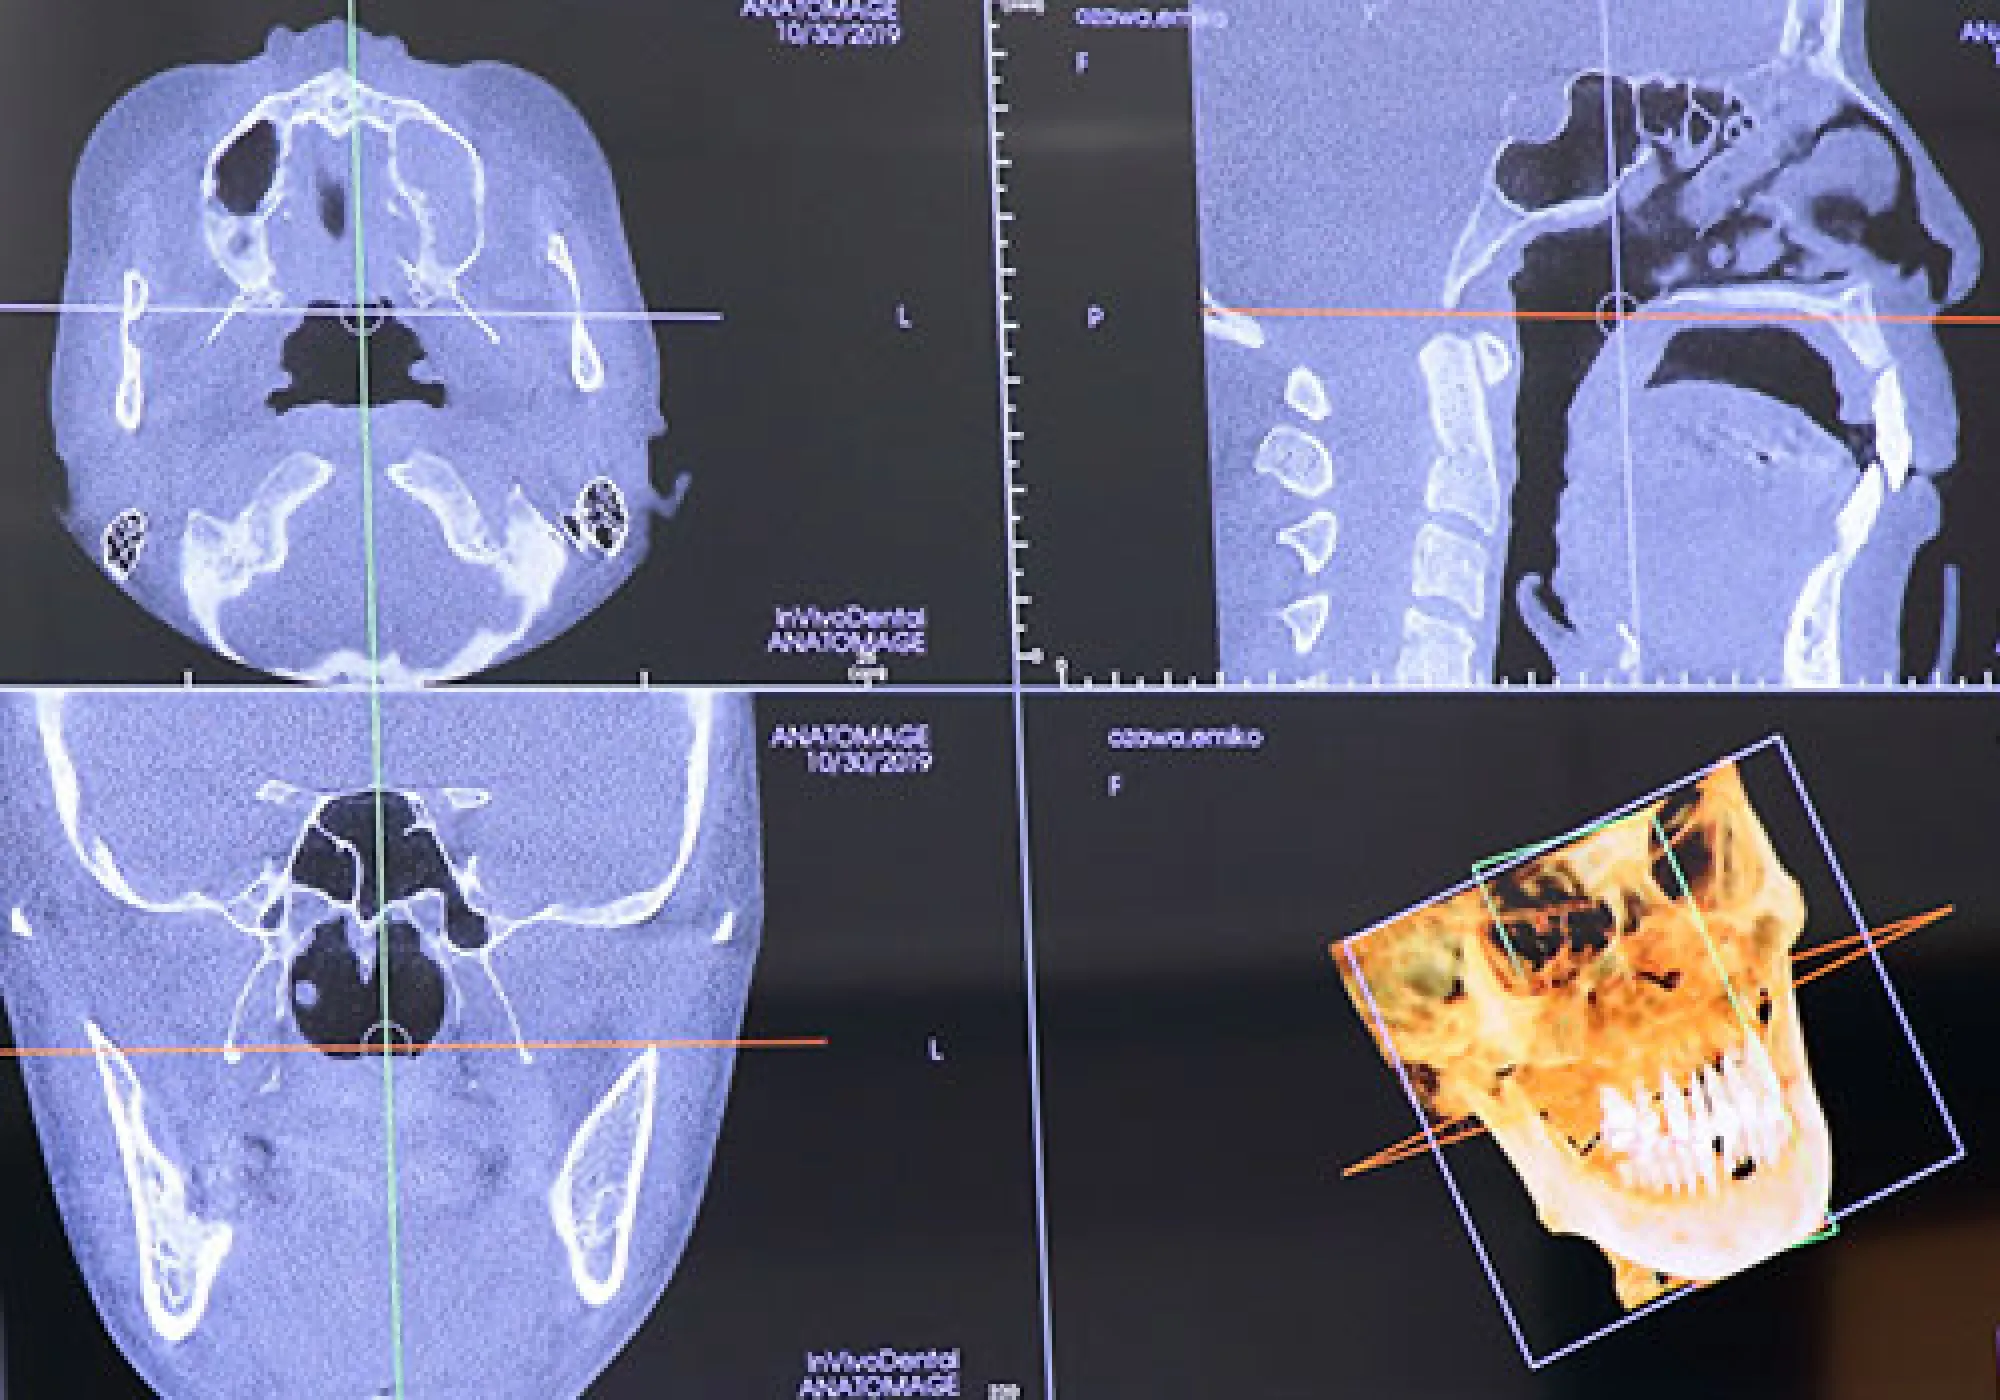

精密検査

当院のインプラント治療に対するこだわり・コンセプトをお伝えし、患者さまに安心して治療を受けていただきたいと思います。 X-Guideとは、インプラント手術を行う際に、インプラントをあらかじめコンピュータ上で決めた位置に確実に埋め込むことができる3Dナビゲーションシステムです。 ナビゲーションを使った手術は、すでに脳神経外科などの細かい部分を扱う分野では使用されているもので、ようやく歯科インプラントの分野でも行えるようになりました。 x-Guideを使用することで、手術中の事故を防いで安全に治療を行うことができるだけでなく、治療の成功率を高めることができる、など多くのメリットがあり、世界の30以上の国々でも高い評価を得ています。 正確なナビゲーションにより、予定したベストな位置にインプラントを埋め込むことができます。また、全ての工程がデジタルで行われることで治療ステップがシンプルになるため、誤差が生じるリスクを最小限に抑えることができます。結果として、治療がより確実なものとなり、治療の成功率を高めることができます。 X-Guideを使った手術では、骨の中の神経や血管の場所や状態をリアルタイムで立体的に把握しながら手術を行うことができます。従来では見えなかった骨の中の状態も、このように確認しながら手術を進められるので、手術中のトラブルや事故を確実に回避できます。 これまで、安全にインプラント手術を行うための前準備として必要であったサージカルテンプレートの製作、調整といったステップを必要としないため、治療までの準備期間が大幅に短くなります。その結果、インプラントをより早く入れることができます。 従来では、ガイデッドサージェリー(サージカルテンプレートを用いた安全なインプラント手術)を行う場合、サージカルテンプレートの厚みでお口を開けている空間が限られてしまい、患者様がお口を開けるのに苦労してしまうことがありました。 もしくは、顎関節症などで口を大きく開けることができない方の場合、手術自体が行えないこともありました。X-Guideシステムを使用するインプラント手術なら、サージカルテンプレートが不要なので、あらゆる患者様に適用することができます。 治療可能な歯科医院が限られている X-Guideは日本においてはまだ新しいシステムであること、また導入に際し多大な費用がかかることから、治療を受けられる歯科医院はまだ少数に限られています。 通常のインプラント手術よりも治療費がかかる 特殊な技術を使用する治療であるため、一般的なインプラント治療と比べると費用がかかります。 LMGでは実際に当院で行ったインプラント手術の症例を公開しております。歯を失ってしまった方や、歯周病等で歯を残すことが困難と診断された方は当院でのインプラント治療なら綺麗で咬みやすい口腔内を取り戻すことができるかもしれません。ぜひチェックしてみてください。世界基準のインプラントやシステムを使用します

インプラントは手術を必要とする治療法ですので、やはりリスクというのは無視できない問題です。数少ないケースでは治療中のトラブルが起こることもありますが、このようなトラブルはしっかりとした設備を備えた歯科医院、治療技術の確かな歯科医師を選ぶことで回避することができます。 インプラント治療は治療を受ける歯科医院によっても大きく結果が変わってきます。当院ではリスク、トラブル回避のためにも様々な対策を行なっています。 インプラントの手術は多かれ少なかれ、誰でも緊張はするものです。ですが、その緊張が極度に達してしまったり、不安感が強いと、気分が悪くなり、血圧の低下、動悸、過呼吸などの症状が現れることがあり、手術の続行が難しくなることがあります。 当院の対策法 インプラント治療は通常の歯科の麻酔で問題なく行えるケースがほとんどですが、歯科恐怖症の方や不安や緊張の強い方は、「静脈内鎮静法」という半分眠ったような状態でリラックスしたまま治療を受けることができます。 あごの骨の中には重要な神経と一緒に大きな血管が走行しています。こちらも事前にしっかりと位置を把握しないで行うと、大量出血を伴う危険性があります。 当院の対策法 当院では、インプラント手術を行う前の精密検査で通常の歯科用レントゲンだけでなく、CTスキャンを行うことにより、あごの骨の内部の神経の走行を把握した上で、安全に治療を行なっていますのでご安心ください。 あごの骨の中には重要な神経と一緒に大きな血管が走行しています。こちらも事前にしっかりと位置を把握しないで行うと、大量出血を伴う危険性があります。 当院の対策法 こちらに関しても、当院のCTスキャンにより位置の把握をした上でガイデッドサージェリー(X-Guide等)による手術をおこないますので、当院ではこのようなことが起こることはありません。 こちらに関しても、CT撮影を行わずにレントゲンだけでインプラント手術を行うと起こるリスクがあります。上あごの歯の上方にある上顎洞と呼ばれる副鼻腔に突き抜けて炎症を起こしてしまう場合もあります。 当院の対策法 CT撮影を行うことで、骨の厚さや形も正確に把握することができます。当院では必ずCT撮影を行ってから適正な位置にインプラントを埋め込みますので、そのような心配はありません。 インプラントを成功に導くためには、いかに細菌感染させないかということが大事になってきます。衛生管理の行き届いていない歯科医院で施術を行うと、細菌感染を起こしてインプラントが早期にダメになる恐れがあります。 当院の対策法 当院では徹底した衛生管理を行っており、院内感染が起こらないよう、最大限に注意を払っておりますので、ご安心ください。 インプラント技術の未熟な歯科医師がインプラント手術を行う際に起こりやすい事故です。あごの骨を削る際に加熱しすぎて骨が火傷をおった状態となり、結果的にインプラントがうまく定着しないことがあります。 当院の対策法 当院では、インプラント治療経験豊富な歯科医師が施術にあたります。ぜひ安心してご来院ください。 インプラントは虫歯にはなりませんが、歯茎から細菌感染を起こして歯周病のような状態になることがあります。これをインプラント周囲炎といいます。インプラント周囲炎は早めに対処しなければ悪化し、放置すると早期にインプラントがダメになってしまいます。 当院の対策法 当院では、「インプラントの被せ物が入ったらそれで治療が終わり」、とは考えていません。インプラントが入った後の管理をいかに行うかで、インプラントの寿命というのが変わってくるからです。長期的に安定するインプラントのためには、定期的なメインテナンスが欠かせません。

X-Guideとは、インプラント手術を行う際に、インプラントをあらかじめコンピュータ上で決めた位置に確実に埋め込むことができる3Dナビゲーションシステムです。 ナビゲーションを使った手術は、すでに脳神経外科などの細かい部分を扱う分野では使用されているもので、ようやく歯科インプラントの分野でも行えるようになりました。 X-Guideを使用することで、手術中の事故を防いで安全に治療を行うことができるだけでなく、治療の成功率を高めることができる、など多くのメリットがあり、世界の30以上の国々でも高い評価を得ています。 正確なナビゲーションにより、予定したベストな位置にインプラントを埋め込むことができます。また、全ての工程がデジタルで行われることで治療ステップがシンプルになるため、誤差が生じるリスクを最小限に抑えることができます。結果として、治療がより確実になります。 X-Guideを使った手術では、骨の中の神経や血管の場所や状態をリアルタイムで立体的に把握しながら手術を行うことができます。従来では見えなかった骨の中の状態も、このように確認しながら手術を進められるので、手術中のトラブルや事故を確実に回避できます。 これまで、安全にインプラント手術を行うための前準備として必要であったサージカルテンプレートの製作、調整といったステップを必要としないため、治療までの準備期間が大幅に短くなります。その結果、インプラントをより早く入れることができます。 従来では、ガイデッドサージェリー(サージカルテンプレートを用いた安全なインプラント手術)を行う場合、サージカルテンプレートの厚みでお口を開けている空間が限られてしまい、患者様がお口を開けるのに苦労してしまうことがありました。X-Guideではそのような問題がありません。 治療可能な歯科医院が限られている X-Guideは日本においてはまだ新しいシステムであること、また導入に際し多大な費用がかかることから、治療を受けられる歯科医院はまだ少数に限られています。 通常のインプラント手術よりも治療費がかかる 特殊な技術を使用する治療であるため、一般的なインプラント治療と比べると費用がかかります。 当院は埼玉県内でも数少ない「難症例」に対応するクリニックです。「難症例」とは、他のクリニックではインプラント手術ができないと言われてしまうケースです。 代表されるのが、顎の骨が薄くインプラントを埋入することができないケースで、こういった患者様の場合、骨質のいい場所を探し出し、ピンポイントで細かくシミュレーションし手術することや、場合によっては骨を作り出してから手術を行うことが必須になります。 残念ながら全ての歯科医院で対応できる内容ではないのが実情です。当院は確立された技術と設備投資により、幅広い患者様の受け入れが可能となっております。 LMGでは実際に当院で行ったインプラント手術の症例を公開しております。歯を失ってしまった方や、歯周病等で歯を残すことが困難と診断された方は当院でのインプラント治療なら綺麗で咬みやすい口腔内を取り戻すことができるかもしれません。ぜひチェックしてみてください。X-Guide(エックスガイド)